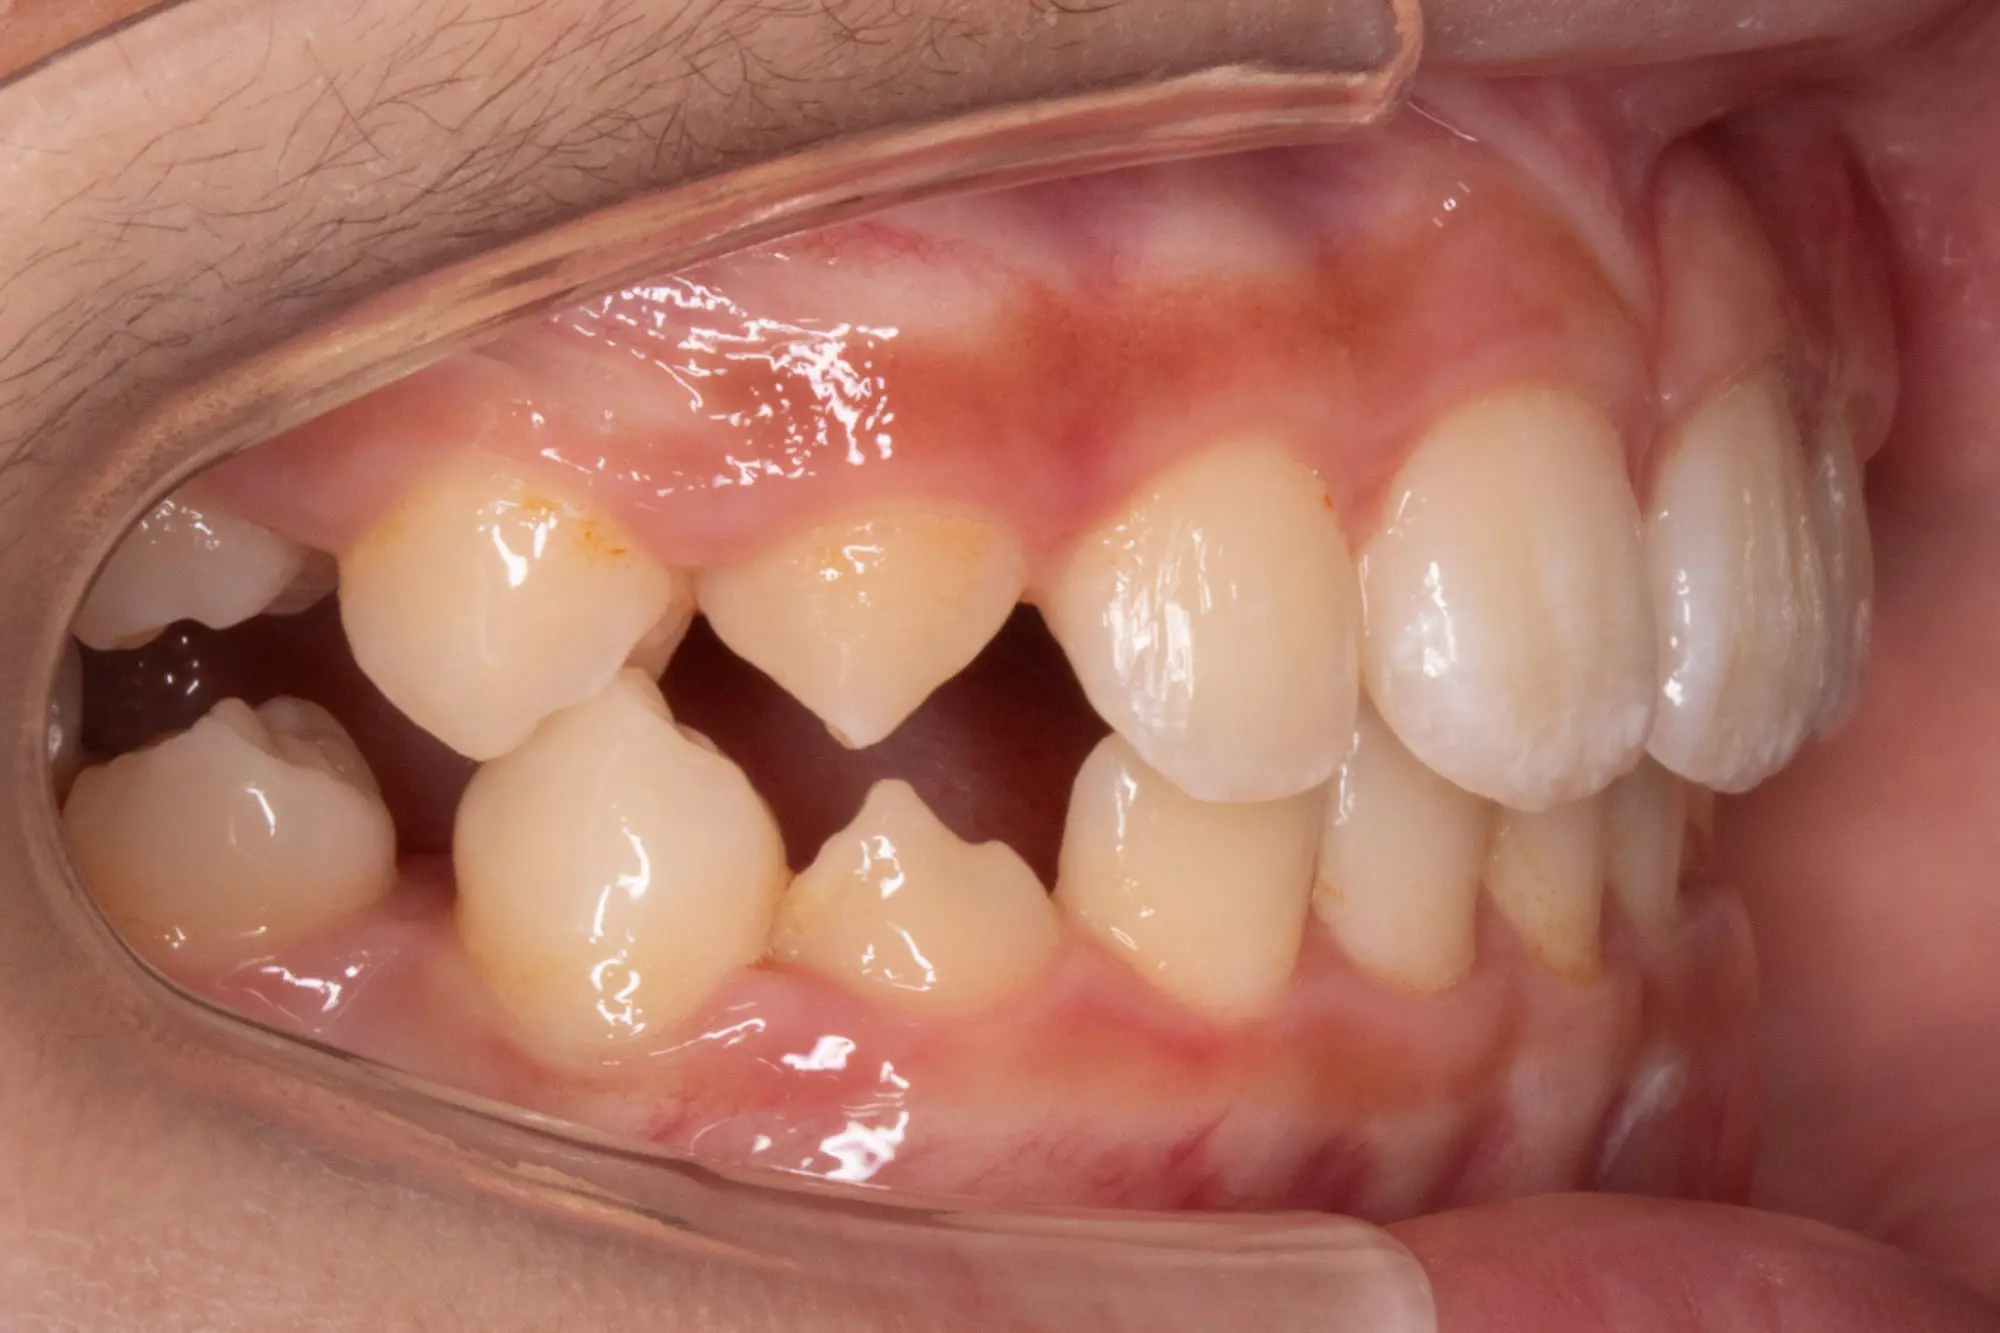

Before

After